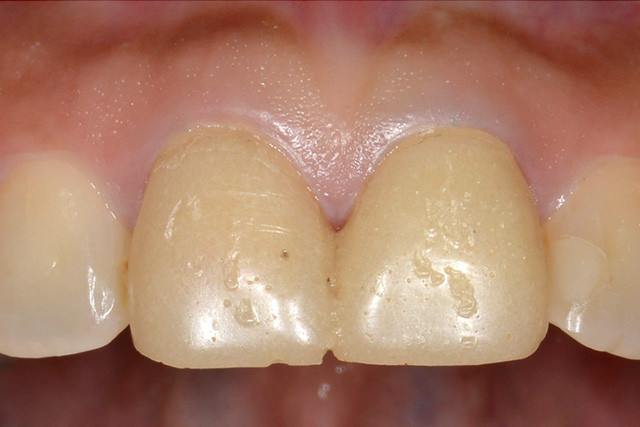

審美症例